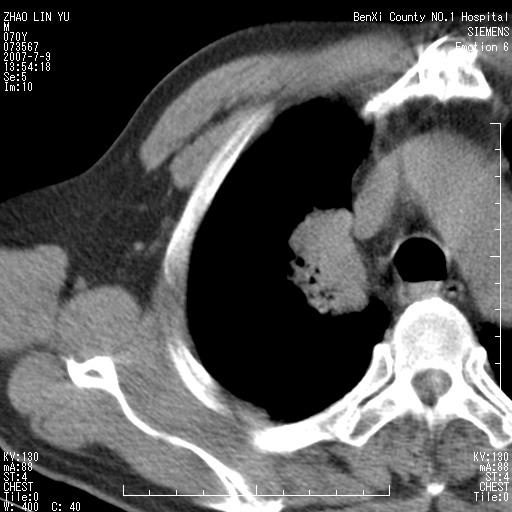

以下是引用王靖旗在2007-7-10 17:12:00的发言:[br] 男、70、咳嗽两个月,半年前换瓣手术,胸片未见异常,于昨天行x片发现右肺上野大片影,行ct扫描,这里是减薄图像,余肺正常。明天晚上会有增强扫描片,到时我会上传。[br][br] 冠状位请大家细看,应该是有意义的,[br][br] 请大家先看平扫发表意见。[br][br]

以下是引用zhangzhongshou在2007-7-10 21:43:00的发言:[br]右肺上叶周围型肺癌,以孤立型细支气管肺泡癌可能性大。